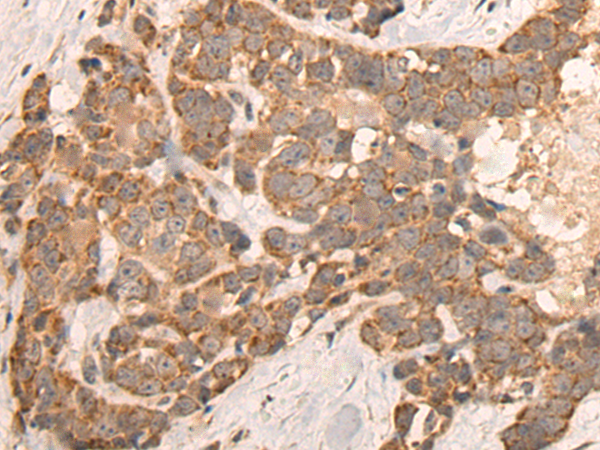

IHC positive control: |

Human thyroid cancer |

IHC Recommend dilution: |

25-100 |